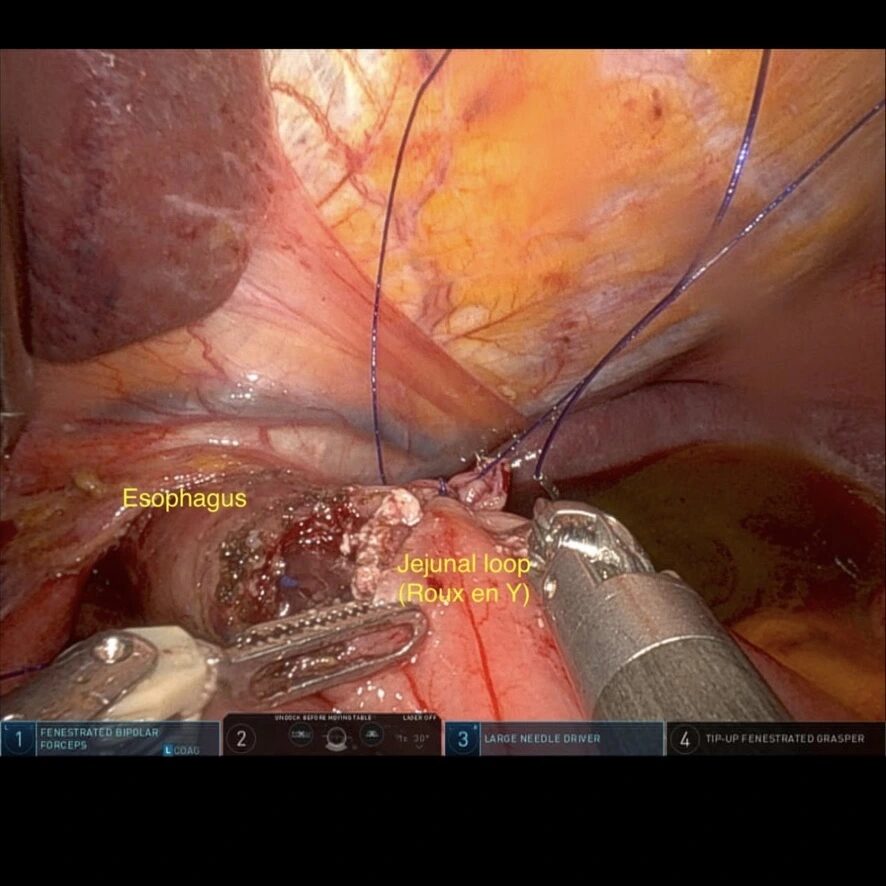

- Realizarea anastomozei eso-jejunale;